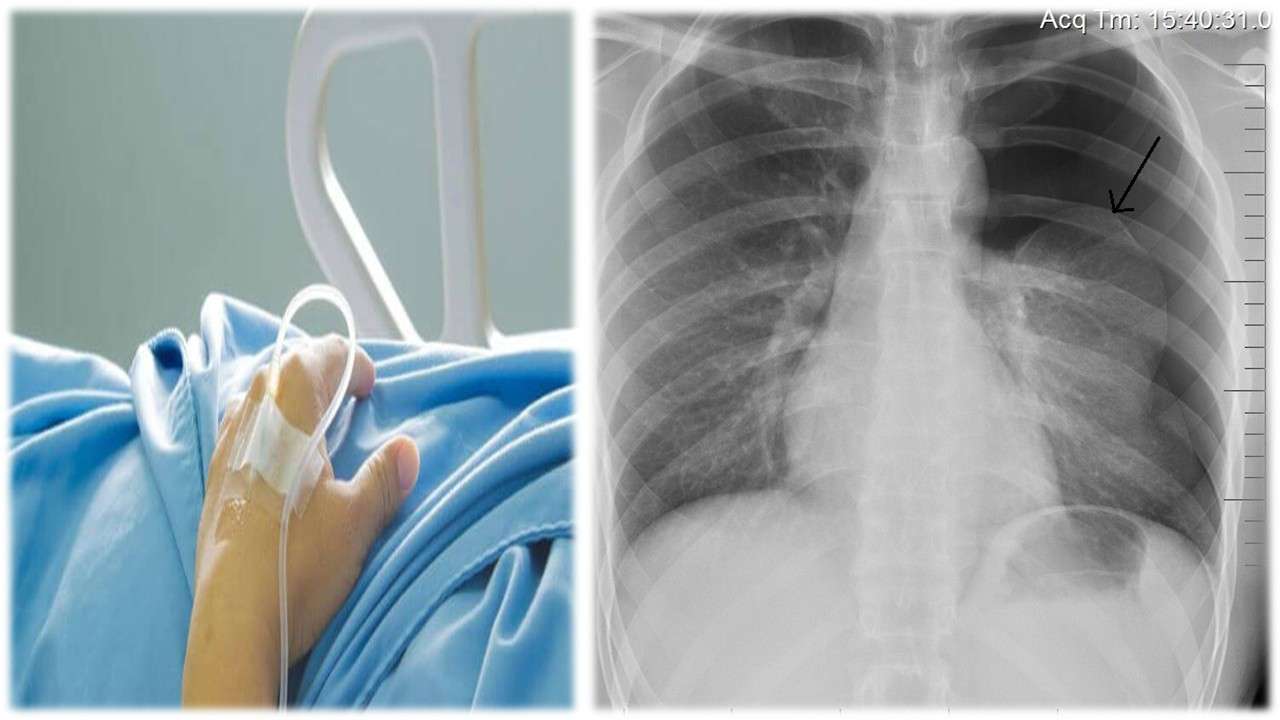

صدى الشعب – أكد مرافق نجل رئيس الوزراء الأسبق، أسعد سعد جمعة أن (جمعة الابن)، دخل في غيبوبة من جديد، دون أن يوضح تفاصيل.

و لكن لاحقاً لعدد من المناشير، بدأها بـ(تم نقل اسعد سعد جمعه للمستشفى الآن إثر نزيف داخلي حاد، الرجاء الدعاء له بالشفاء العاجل، ليكمل في منشور آخر بعد دقائق: “يؤسفني اخباركم بأن قلب السيد أسعد توقف والأطباء يسعون لانعاشه كهربائياً.”

ثم أخيراً في شرح حالته الصحية التي يُرثى لها قال: “الحمد والشكر لله، بدأ قلب اسعد سعد جمعه بالنبض ،ولكن تم كسر ضلعين لأنهم اضطروا لاستعمال ٤٥٠ ك جول.

يذكر أن نجل رئيس الوزراء الأسبق، خرج في الكثير من المواقع الإلكترونية و المؤسسات الإعلامية، مشيراً أنها تعرض للظلم من أشخاص بعينهم، حرموه من ورثة والده، ألأمر الذي جعله حبيس المنزل للمطالبات المالية و حباس المستشفيات و أسرة (الـicu , ccu)..